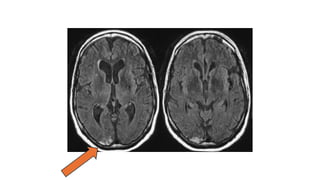

• #19 Large cup healthy rim = not glaucoma Normal mri

• #21 +ve phenomenon: flashes